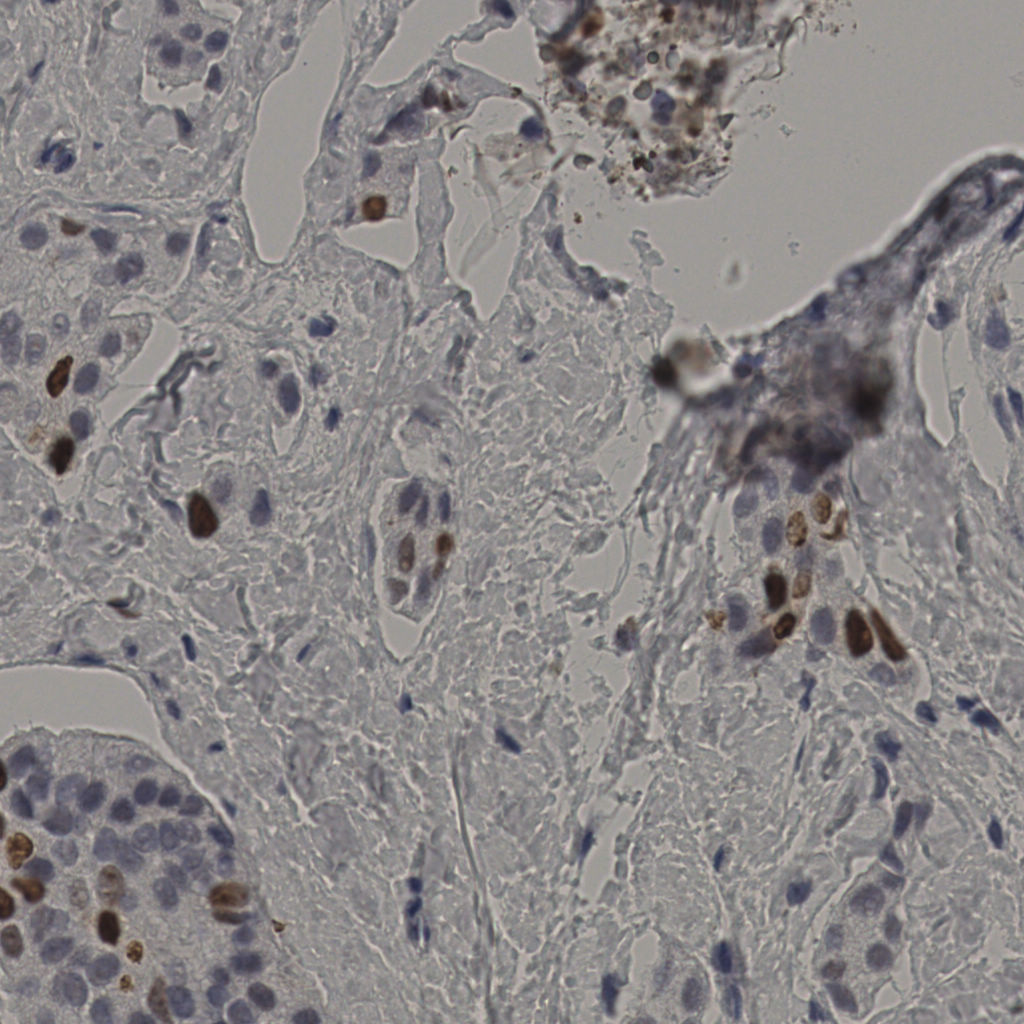

slice_38_10_x34048_y8960.png

slice_38_10_x3404...